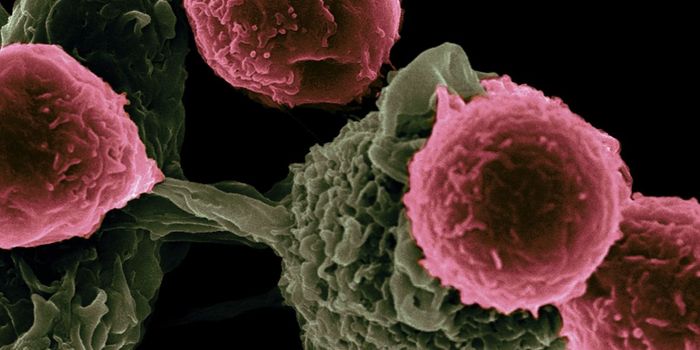

DEC 10, 2015ImmunologySuperior technology brings us novel images of cancer cells and lymphocytes this week, and now scientists can learn more ...

NOV 20, 2019ImmunologyManipulating the immune system’s population of natural killer cells could bolster therapies targeting cancer. A ne ...

SEP 17, 2015ImmunologyCancer immunotherapy efforts have been mainly concentrated on the adaptive immune system, some even connecting epigeneti ...

JUN 27, 2016ImmunologyT cells are the body’s natural fleet of cancer-attacking lymphocytes, but in recent years scientists have found a ...